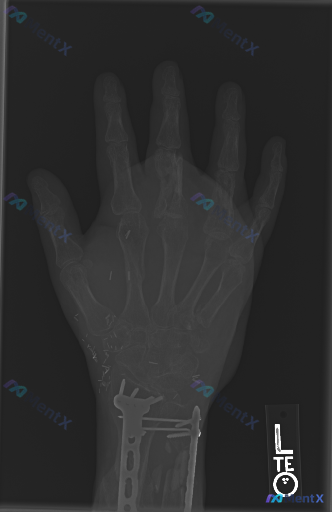

整理到一组左手及腕部的影像资料,和大家一起读片讨论。 基本影像背景 - 这是左手及腕关节的X线平片(正位像)。 - 患者有左侧桡骨远端手术史。 影像观察到的客观表现 1. 内固定装置:左侧桡骨及尺骨远端可见钢板、螺钉在位,提示既往术后状态。 2. 掌骨:左手中指(第三掌骨)远端骨干区域有明确的骨质连...